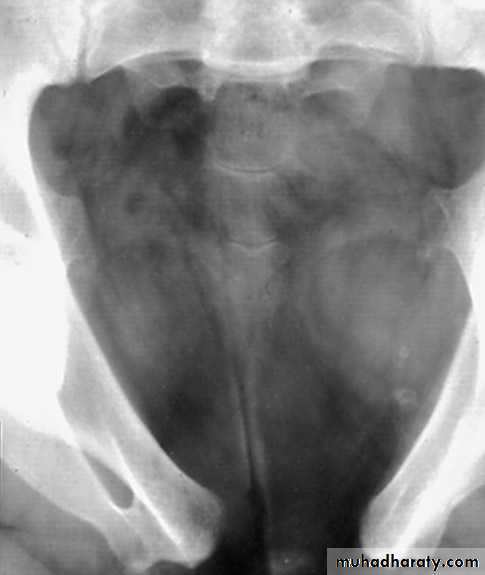

Infantile hydronephrosis ( PUJ OBSTRUCTION ):

IVU shows :

Marked dilatation of pelvis and may be extra-renal.

Calyceal dilatation is late and in advanced cases form foot shape PCS

The ureter is not seen and when it is seen looksnormal .

Delayed film with I.V. diuretic produce gross dilatation .